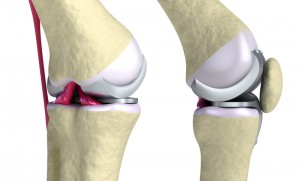

térdprotézis

Mindezek gyártók holding, amelyben több ország vesz részt. Különösen Oroszország szállítja a legjobb titánötvözetek és gyártási eljárások révén a legmagasabb az USA-ban, Németországban, Izraelben. A arzenáljának ortopédia ma, számos különböző modell ízületek - a nagyobb csípő-, hogy a legkisebb interphalangealis, különböző méretű és különféle anyagokból készülhetnek: titánötvözetek, kombinálva a kerámia bevonat, polimer anyagok. A kiválasztás a protézis az egyéni teljesítményt, általában kérés egy adott beteg számára. Műveletek esetében a térdízület protézis nők egy különleges protézist, figyelembe véve a női test az alkotmányos jellemzői.

Van 2 fajta csontpótlás: teljes (full) és részleges. Ha a teljes csere a teljes eltávolítását a közös végezzük amputáció a disztális csont és beültethetők általa választott protézis. Részleges protézis - egy fiatalos megközelítés, csak a változás az izületi felületek, ez az úgynevezett resurfeysingom. Ennek lényege lényege, hogy eltávolítjuk a kopott felület a porc és a rögzítő egy mesterséges helyettesítheti azokat - a speciális kerámia, vagy nagy szilárdságú polimerek, kopott a előkészített csont és reteszelt típus fogászati korona. Az ilyen műveletek kevésbé traumatikus, és egyre többen használják a gyakorlatban.